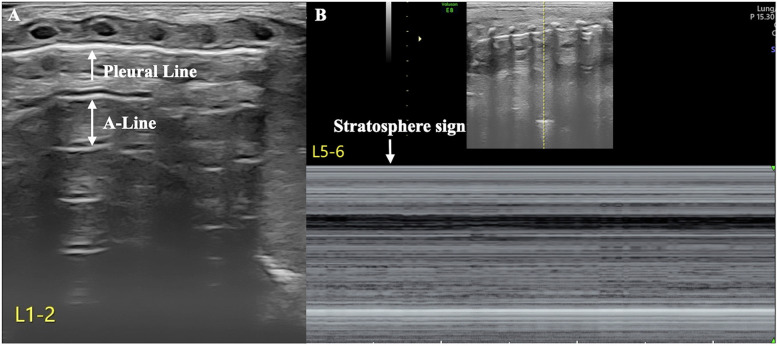

目前,肺超声(LUS)在世界范围内广泛用于诊断新生儿气胸(PTX)和胸腔积液等疾病,这两种疾病都是新生儿期常见的疾病。然而,两种情况并存或同时发生,即气胸积液,在临床上比较少见。超声可提供可靠的诊断,并可用于指导和监测适当的治疗。在这个病例报告中,我们描述了一个新的超声征象,气液点,我们建议作为诊断新生儿气胸的特殊征象。

Currently, lung ultrasound (LUS) is widely used worldwide for the diagnosing conditions such as neonatal pneumothorax (PTX) and pleural effusion, which are both common conditions during the neonatal period. However, the coexistence or simultaneous occurrence of both conditions, namely, hydropneumothorax, is relatively rare in clinical practice. Ultrasound enables a reliable diagnosis and can be used to guide and monitor appropriate treatment. In this case report, we describe a new ultrasound sign, the air-fluid point, which we propose as a specific sign for the diagnosis of neonatal hydropneumothorax.